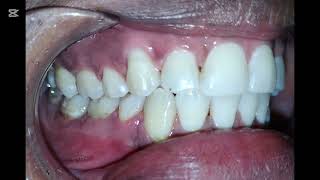

Treatment Planning| Anterior Open Bite | Spaces Non - Extraction Braces Treatment #braces #dentistry